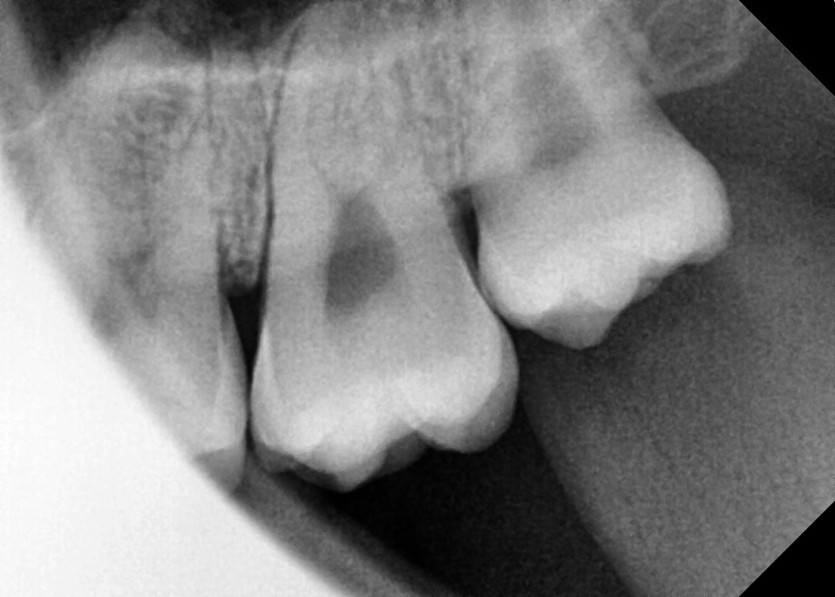

#18,28,38,48 사랑니 발치

구강 외과 전문의가 당일 발치했습니다.